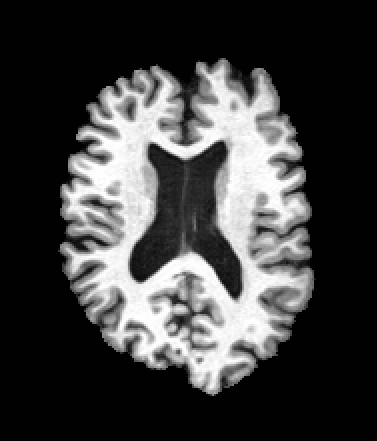

A trained MetaVoxel model can be unconditionally sampled by drawing Gaussian or categorical noise for each variable at timestep , and iteratively apply the denoising network until reaching . Unlike conventional diffusion models that focus solely on image generation, MetaVoxel can generate coherent synthetic patient profiles from the joint distribution , as shown in Figure 2.

| Age: 64.0 | Age: 53.8 | Age: 70.9 | Age: 76.9 |

| Sex: Male | Sex: Female | Sex: Female | Sex: Male |

![]() |

| Age: 80.9 | Age: 77.7 | Age: 73.2 | Age: 84.6 |

| Sex: Male | Sex: Female | Sex: Female | Sex: Female |